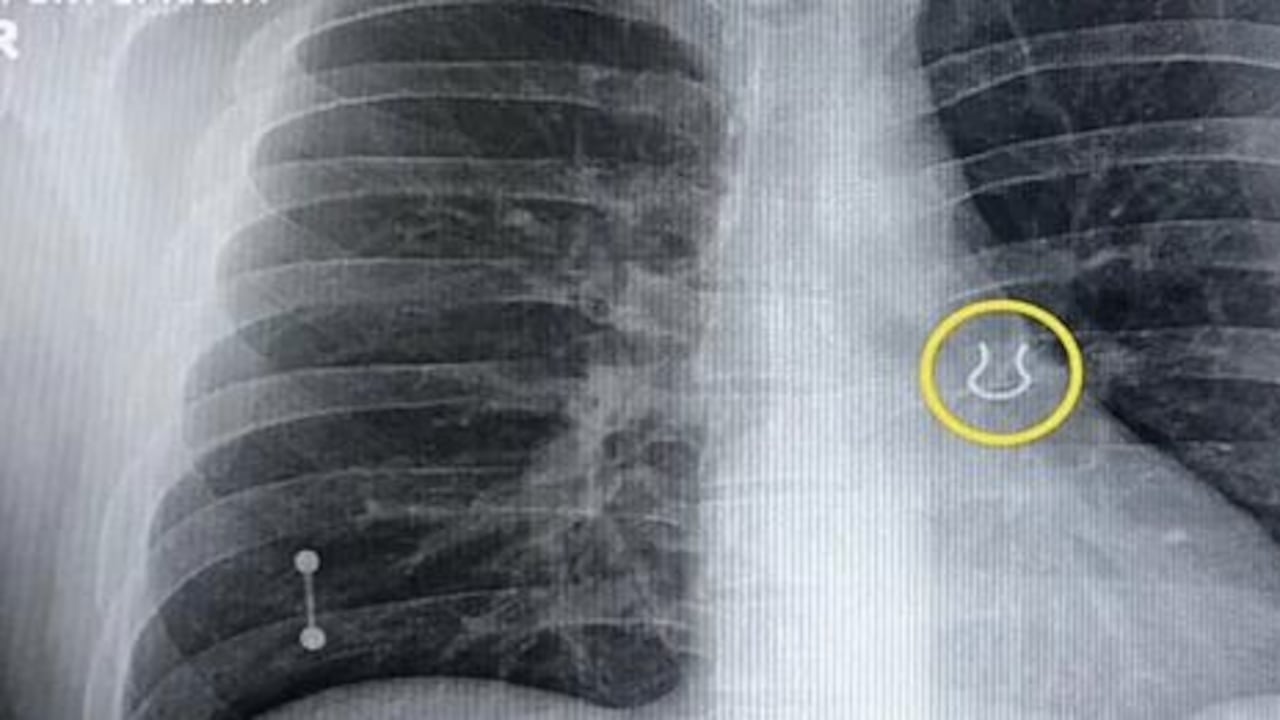

Al realizar las imágenes de rutina en sus pulmones, los médicos dieron con un sorprendente hallazgo. Todo se debía a un ‘piercing’ de nariz que el paciente había perdido hace cinco años y se encontraba alojado en el sistema respiratorio.

Joey Lykins, de 35 años de edad, es el protagonista de esta curiosa historia. Los especialistas que atendieron el caso sospechaban de una neumonía, pero las imágenes revelaron la presencia de un pendiente de aproximadamente 0,6 pulgadas.

Cinco años después, el hombre se volvería a encontrar con su accesorio, pero esta vez se encontraba alojado dentro del lóbulo superior izquierdo de su pulmón. Joey Lykins sospecha que pudo haber inhalado la pieza cuando se encontraba durmiendo.